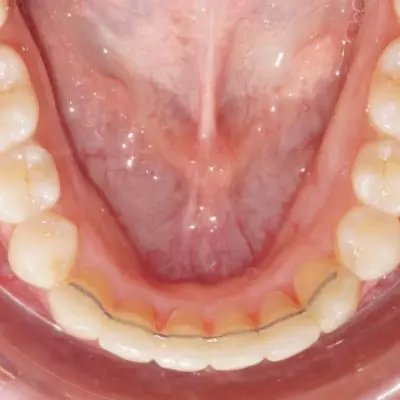

La contention orthodontique constitue une phase cruciale à la suite d’un traitement orthodontique, car elle permet de préserver les résultats obtenus. Nous vous offrons des contentions sur mesure,  réalisée dans notre cabinet par un robot , après une empreinte numérique . Cette méthode personnalisée garantit une finition parfaite pour chaque patient.Chez les adolescents, la contention est  placée sur l’arcade inférieure et, si nécessaire, sur l’arcade supérieure. Pour les adultes, la contention est appliquée sur les deux arcades, supérieure et inférieure.

fil de contention collée Pornic